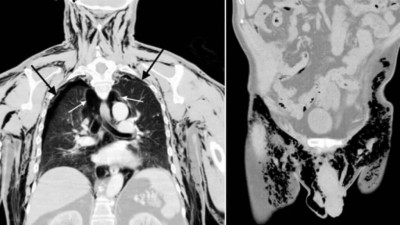

Um exame descobriu que ambos os pulmões do idoso entraram em colapso e ele tinha muito ar circulando dentro do peito, o que provavelmente foi o que causou a sua queixa.

O paciente passou três dias no hospital, onde os médicos liberaram constantemente o ar preso no corpo do idoso. Eles trataram seus pulmões colapsados (pneumotórax) e ele também recebeu antibióticos e procedimentos de urologia para sua ferida escrotal.